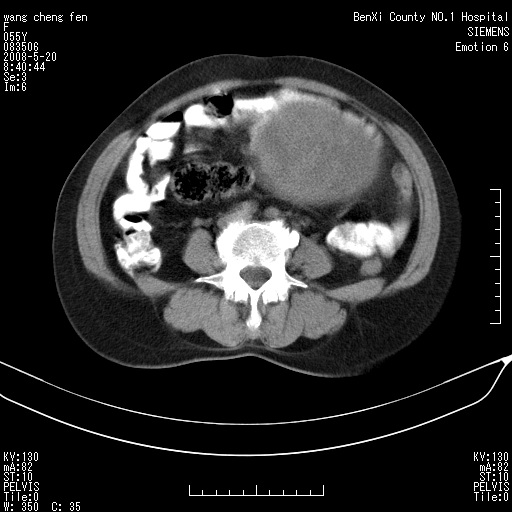

女、绝经后阴道流血3个月

左侧附件区可见一囊性占位,边缘清楚,内可见不规则形软组织影 ce:囊壁及内部可见强化 考虑 卵巢囊腺瘤

左侧附件区巨大囊实性病灶,边缘光整,病灶囊壁较厚,增强示囊壁及实性部分明显强化,强化呈度与宫体实质大致相同,宫腔积液征像,未见盆腔积液等其他异常,考虑左侧卵巢囊腺癌,不除外囊腺瘤及浆膜下肌瘤坏死

左侧附件区巨大囊实性病灶,边缘光整,病灶囊壁较厚,增强示囊壁及实性部分明显强化,强化呈度与宫体实质大致相同,宫腔积液征像,未见盆腔积液等其他异常。绝经后阴道流血3个月,结合病史左侧卵巢囊腺癌首先考虑,宫腔扩大不除外累及。期待结果。

支持浆膜下子宫肌瘤.之前由于网络原因未看全图片,现在重看,宫颈见一类圆形低密度影,增强轻度强化,低于肌层强化,宫腔扩大,考虑宫颈癌伴宫腔积液可能性大.

囊实性肿块分隔厚度较大,厚薄不均,增强实性成分明显强化,有不规则阴道流血,卵巢囊腺癌可能性大。

1,宫颈部占位,宫颈癌?2,左侧附件区囊实性占位,界较清,实质部分强化明显。考虑浆膜下或阔韧带肌瘤囊变可能大。囊腺类肿瘤不除外。